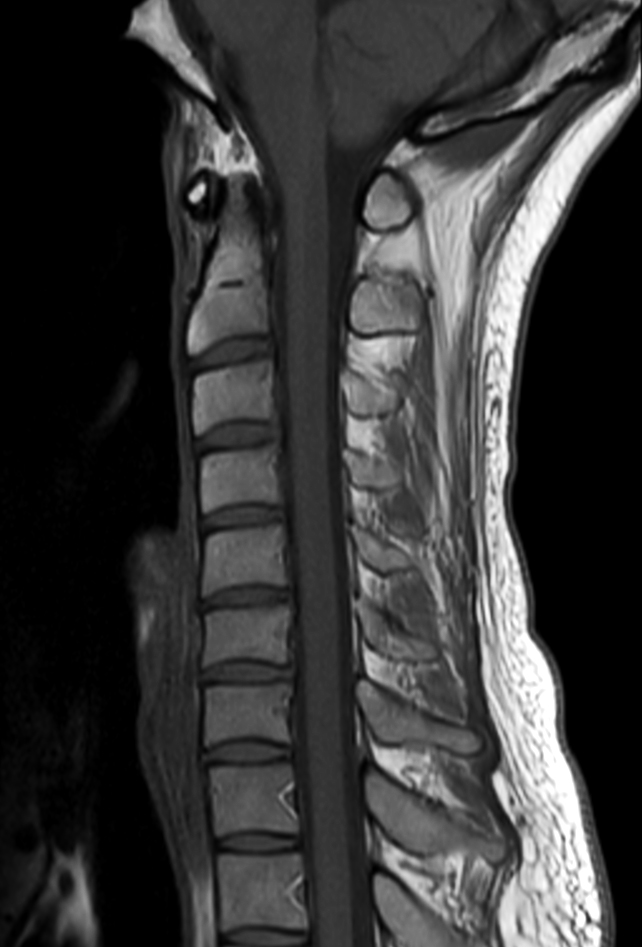

Sagittal T1w mDIXON TSE (In Phase)

Sagittal T1w mDIXON TSE (Water)